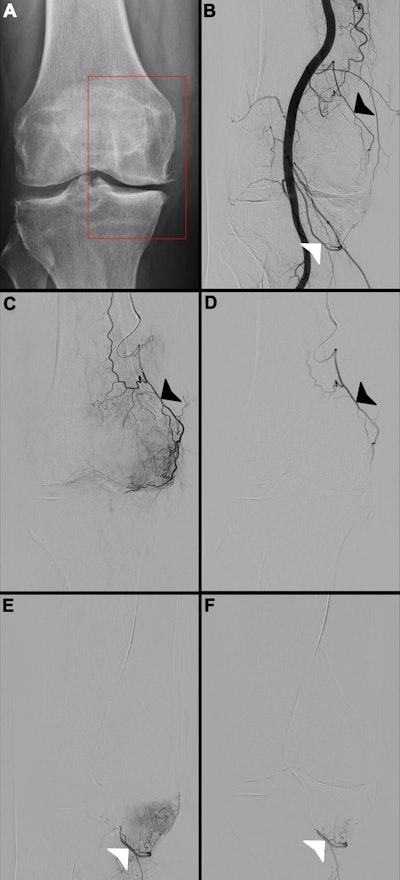

Images in a 65-year-old female patient. (A) Radiograph of the right knee shows Kellgren-Lawrence grade 3 knee osteoarthritis, with chronic pain localized to the medial compartment (red box). (B) Digital subtraction angiogram of the popliteal artery helps identify two potential target arteries: the superior medial genicular artery (black arrowhead) and the inferior medial genicular artery (white arrowhead). (C, E) Selective, pre-embolization digital subtraction angiograms of the superior medial genicular artery (black arrowhead in C) and the inferior medial genicular artery (white arrowhead in E) demonstrate a hyperemic blush in the medial compartment, indicative of pathologic hypervascularity. (D, F) Postembolization digital subtraction angiograms show successful stasis in the superior medial genicular artery (black arrowhead in D) and the inferior medial genicular artery (white arrowhead in F), with complete resolution of the hyperemic blush.RSNA